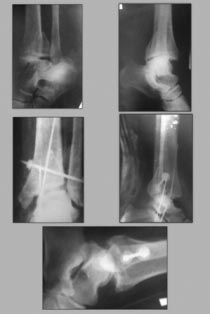

Больной Г. 1960г.р. Травму получил 2 месяца тому назад, прооперирован в областной клинике.

Сейчас удалены трансартикулярные спицы. Снята гипсовая повязка. В обл. голеностопного сустава отёк держится. У меня возникли вопроси в правильности проведенной операции.Прошу вашего совета. Рентген снимок прилагается.

Наружная лодыжка "недотянута". Задний край не репонирован. Конгруентность сустава ......

На снимках, конечно, мало, что видно, но тем не менее:

1) Методика болта-стяжки порочна и, как мне казалось, давно не применяется

2) Методика трансартикулярной фиксации спицами тоже порочна

3) таранная кость в наружном подвывихе, синдесмоз не восстановлен анатомично

4) длина малоберцовой кости не восстановлена

5) большой и клинически значимый фрагмент заднего края не репонирован

Исход такого синтеза - тяжелый артроз, развивающийся в течение нескольких лет заканчивающийся, как правило, вынужденным артродезом.

В отношении необходимости остеотомии малоберцовой кости с восстановлением ее длины согласен.Не уверен, что получится устранить наружный подвывих, не открывая медиальный отдел голеностопа и синдесмоз, заполненные рубцовой тканью.

Насчет возможности анатомичного восстановления суставной повехности тибии совсем не уверен.